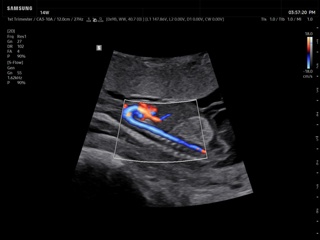

Atlas of ultrasound images - obsterics

In the section "Оbsterics" of atlas the results of ultrasonic examinations of pregnant women with different durations of gestation are represented. Here you can see images of internally organs, cerebrum, cordis and the sex of the fetus, the sonograms of multiple pregnancy, the blood flow in placenta and umbilical cord, defects of fetal`s development, etc.